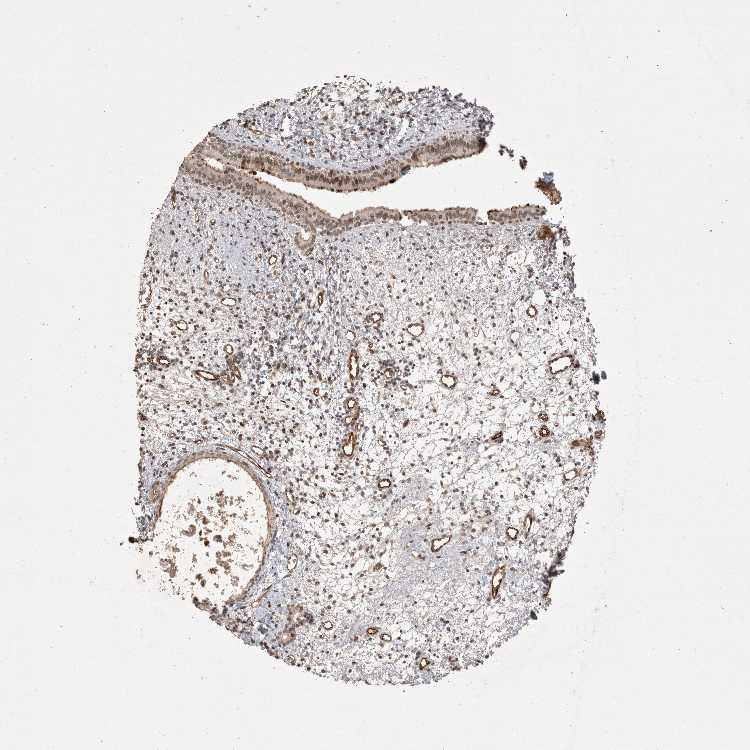

CDC14B